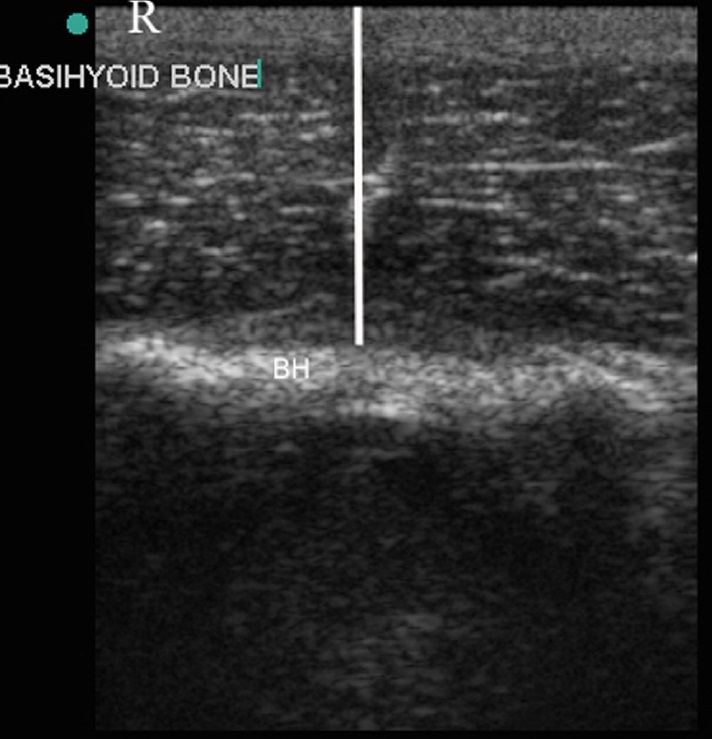

Fig 7: Transverse plane ultrasound of the basihyoid bone

(arrowheads) and the ceratohyoid bones (arrows) of a

normal larynx, obtained with the transducer positioned

ventrally. Left is to the right of the image and right is to the

left

A significant relationship was found between the depth of the basihyoid bone at rest and the occurrence of dorsal displacement of the soft palate at exercise whereby on average a more ventral location of the basihyoid bone is present in horses with dorsal displacement of the soft palate. Chalmers 2009 VRU

basihyoid bone depth at the level of lingual process

A

basihyoid depth is smaller in horses with DDSP